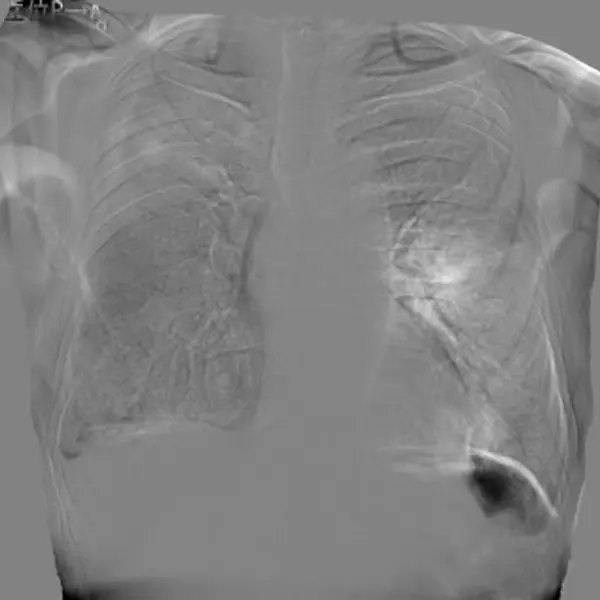

胸部AI解析と画像処理技術の併用により見落とし防止や確信度向上に貢献します。

胸部X線画像診断支援AI

胸部骨減弱処理「Bone Suppression処理」

胸部経時差分処理「Temporal Subtraction処理」